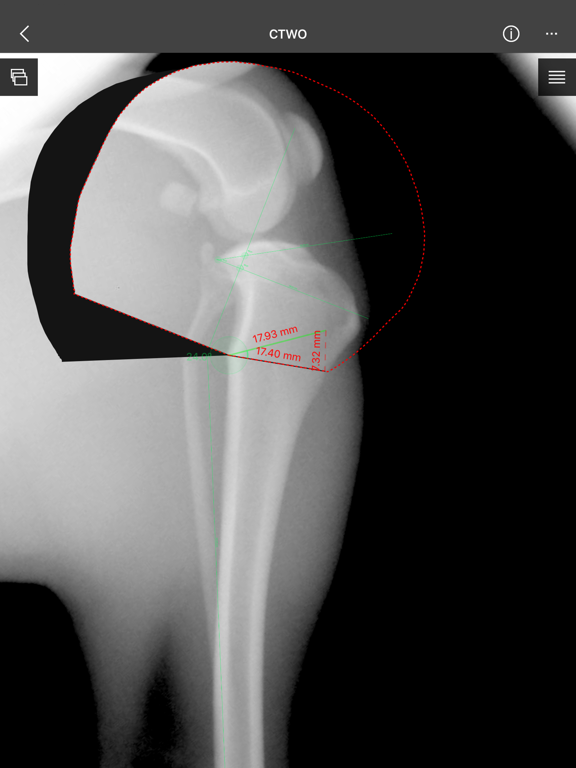

a) Linear Measure.

b) Radial measure/Circle draw.

c) Angle measure/Triangle draw.

e) Wedge cut, CTWO and angular osteotomies.